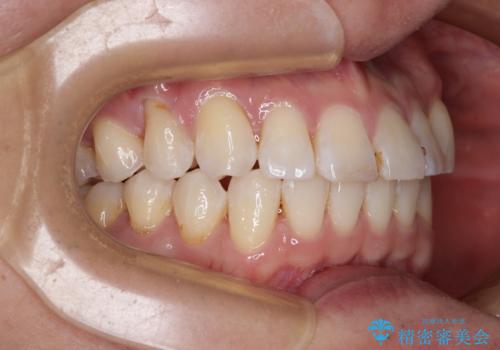

咬合平面改善のため、アンカースクリューを多用し、ワイヤー装置にて矯正治療を行うこととしました。

動きにくい歯はやはり動きにくく、咬み合わせ改善に時間を要しましたが、患者様には大変満足していただけました。